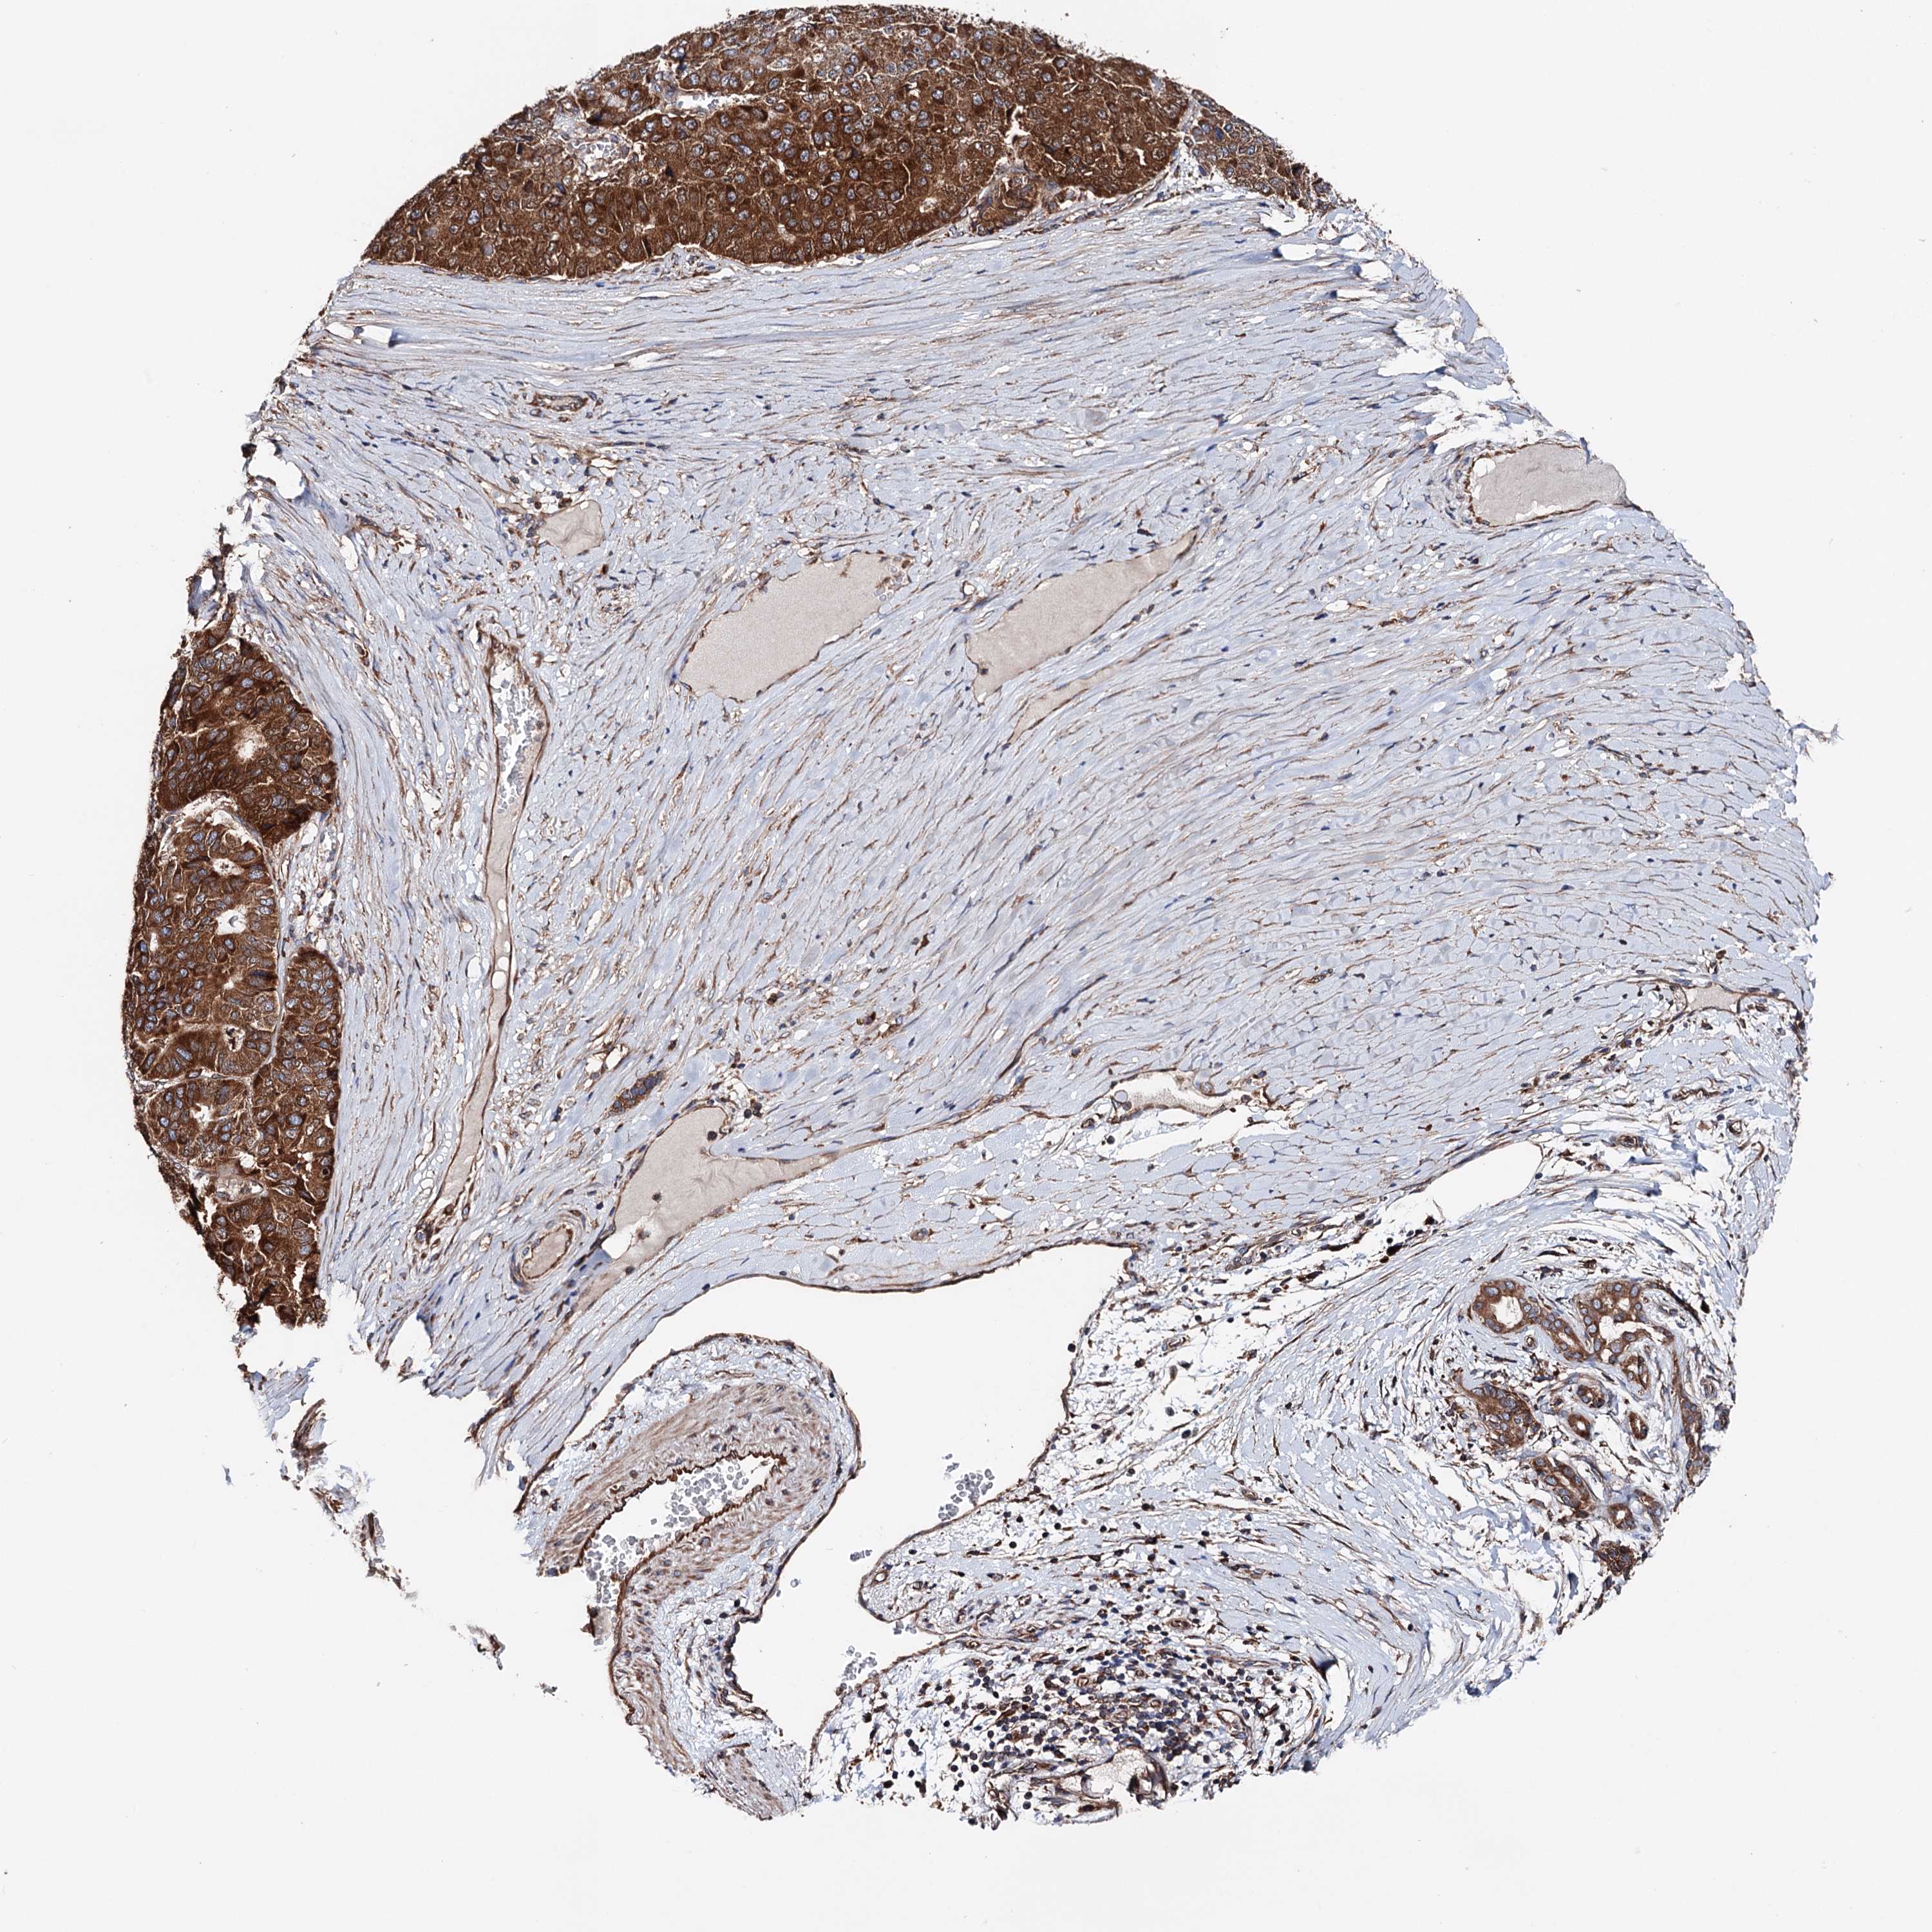

PANCREATIC CANCER - Protein expressioni

A mouse-over function shows sample information and annotation data. Click on an image to view it in a full screen mode. Samples can be filtered based on level of antibody staining by selecting one or several of the following categories: high, medium, low and not detected. The assay and annotation is described here.

Note that samples used for immunohistochemistry by the Human Protein Atlas do not correspond to samples in the TCGA dataset.

Antibody stainingi

Antibody staining in the annotated cell types in the current human tissue is reported as not detected, low, medium, or high, based on conventional immunohistochemistry profiling in selected tissues. This score is based on the combination of the staining intensity and fraction of stained cells.

Each image is clickable and will lead to virtual microscopy that enables deeper exploration of all samples and also displays staining intensity scores, fraction scores and subcellular localization as well as patient and tissue information for each sample.

Antibody HPA039363

Antibody HPA039456

Staining

High

Medium

Low

Not detected

Intensity

Strong

Moderate

Weak

Negative

Quantity

>75%

75%-25%

<25%

None

Location

Nuclear

Cytoplasmic/membranous

Cytoplasmic/membranous,nuclear

Adenocarcinoma, NOS